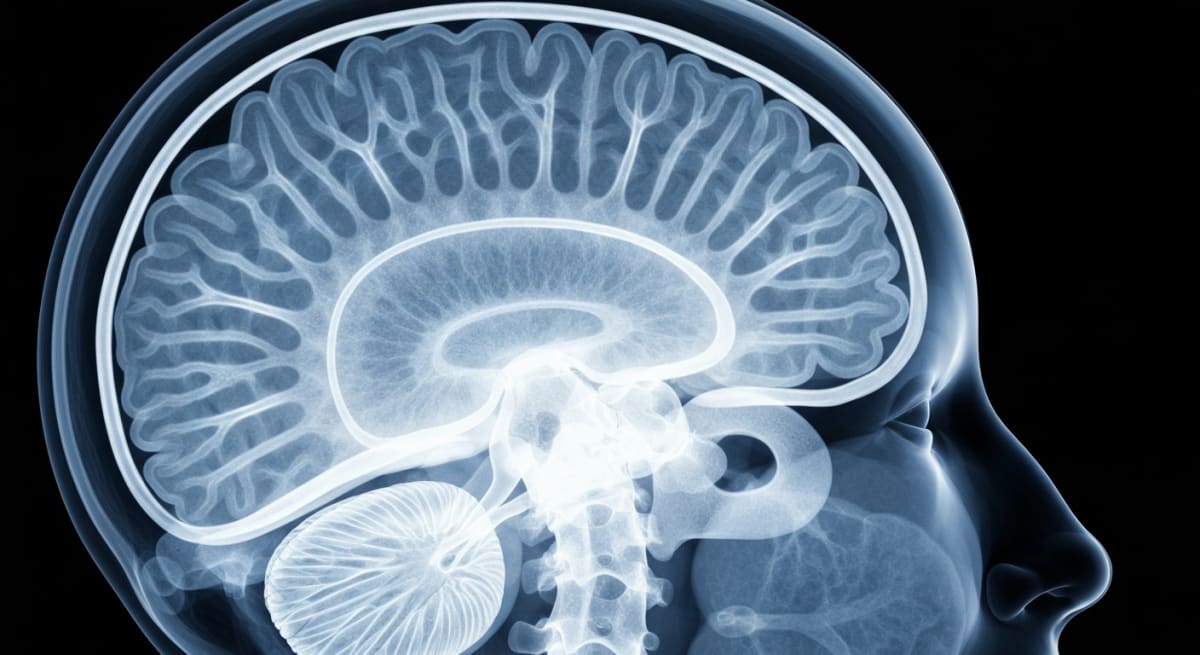

The new treatment King Crews underwent uses ultrasound waves guided by MRI to target specific brain areas controlling movement. Unlike traditional deep brain stimulation surgery, this approach requires no incisions and carries no surgical bleeding risk.

The FDA approved the bilateral therapy in July 2025, allowing treatment on both sides of the brain six months apart. Dr. Joel Salinas, a Harvard-trained neurologist, calls it a "meaningful advance for the right patients."